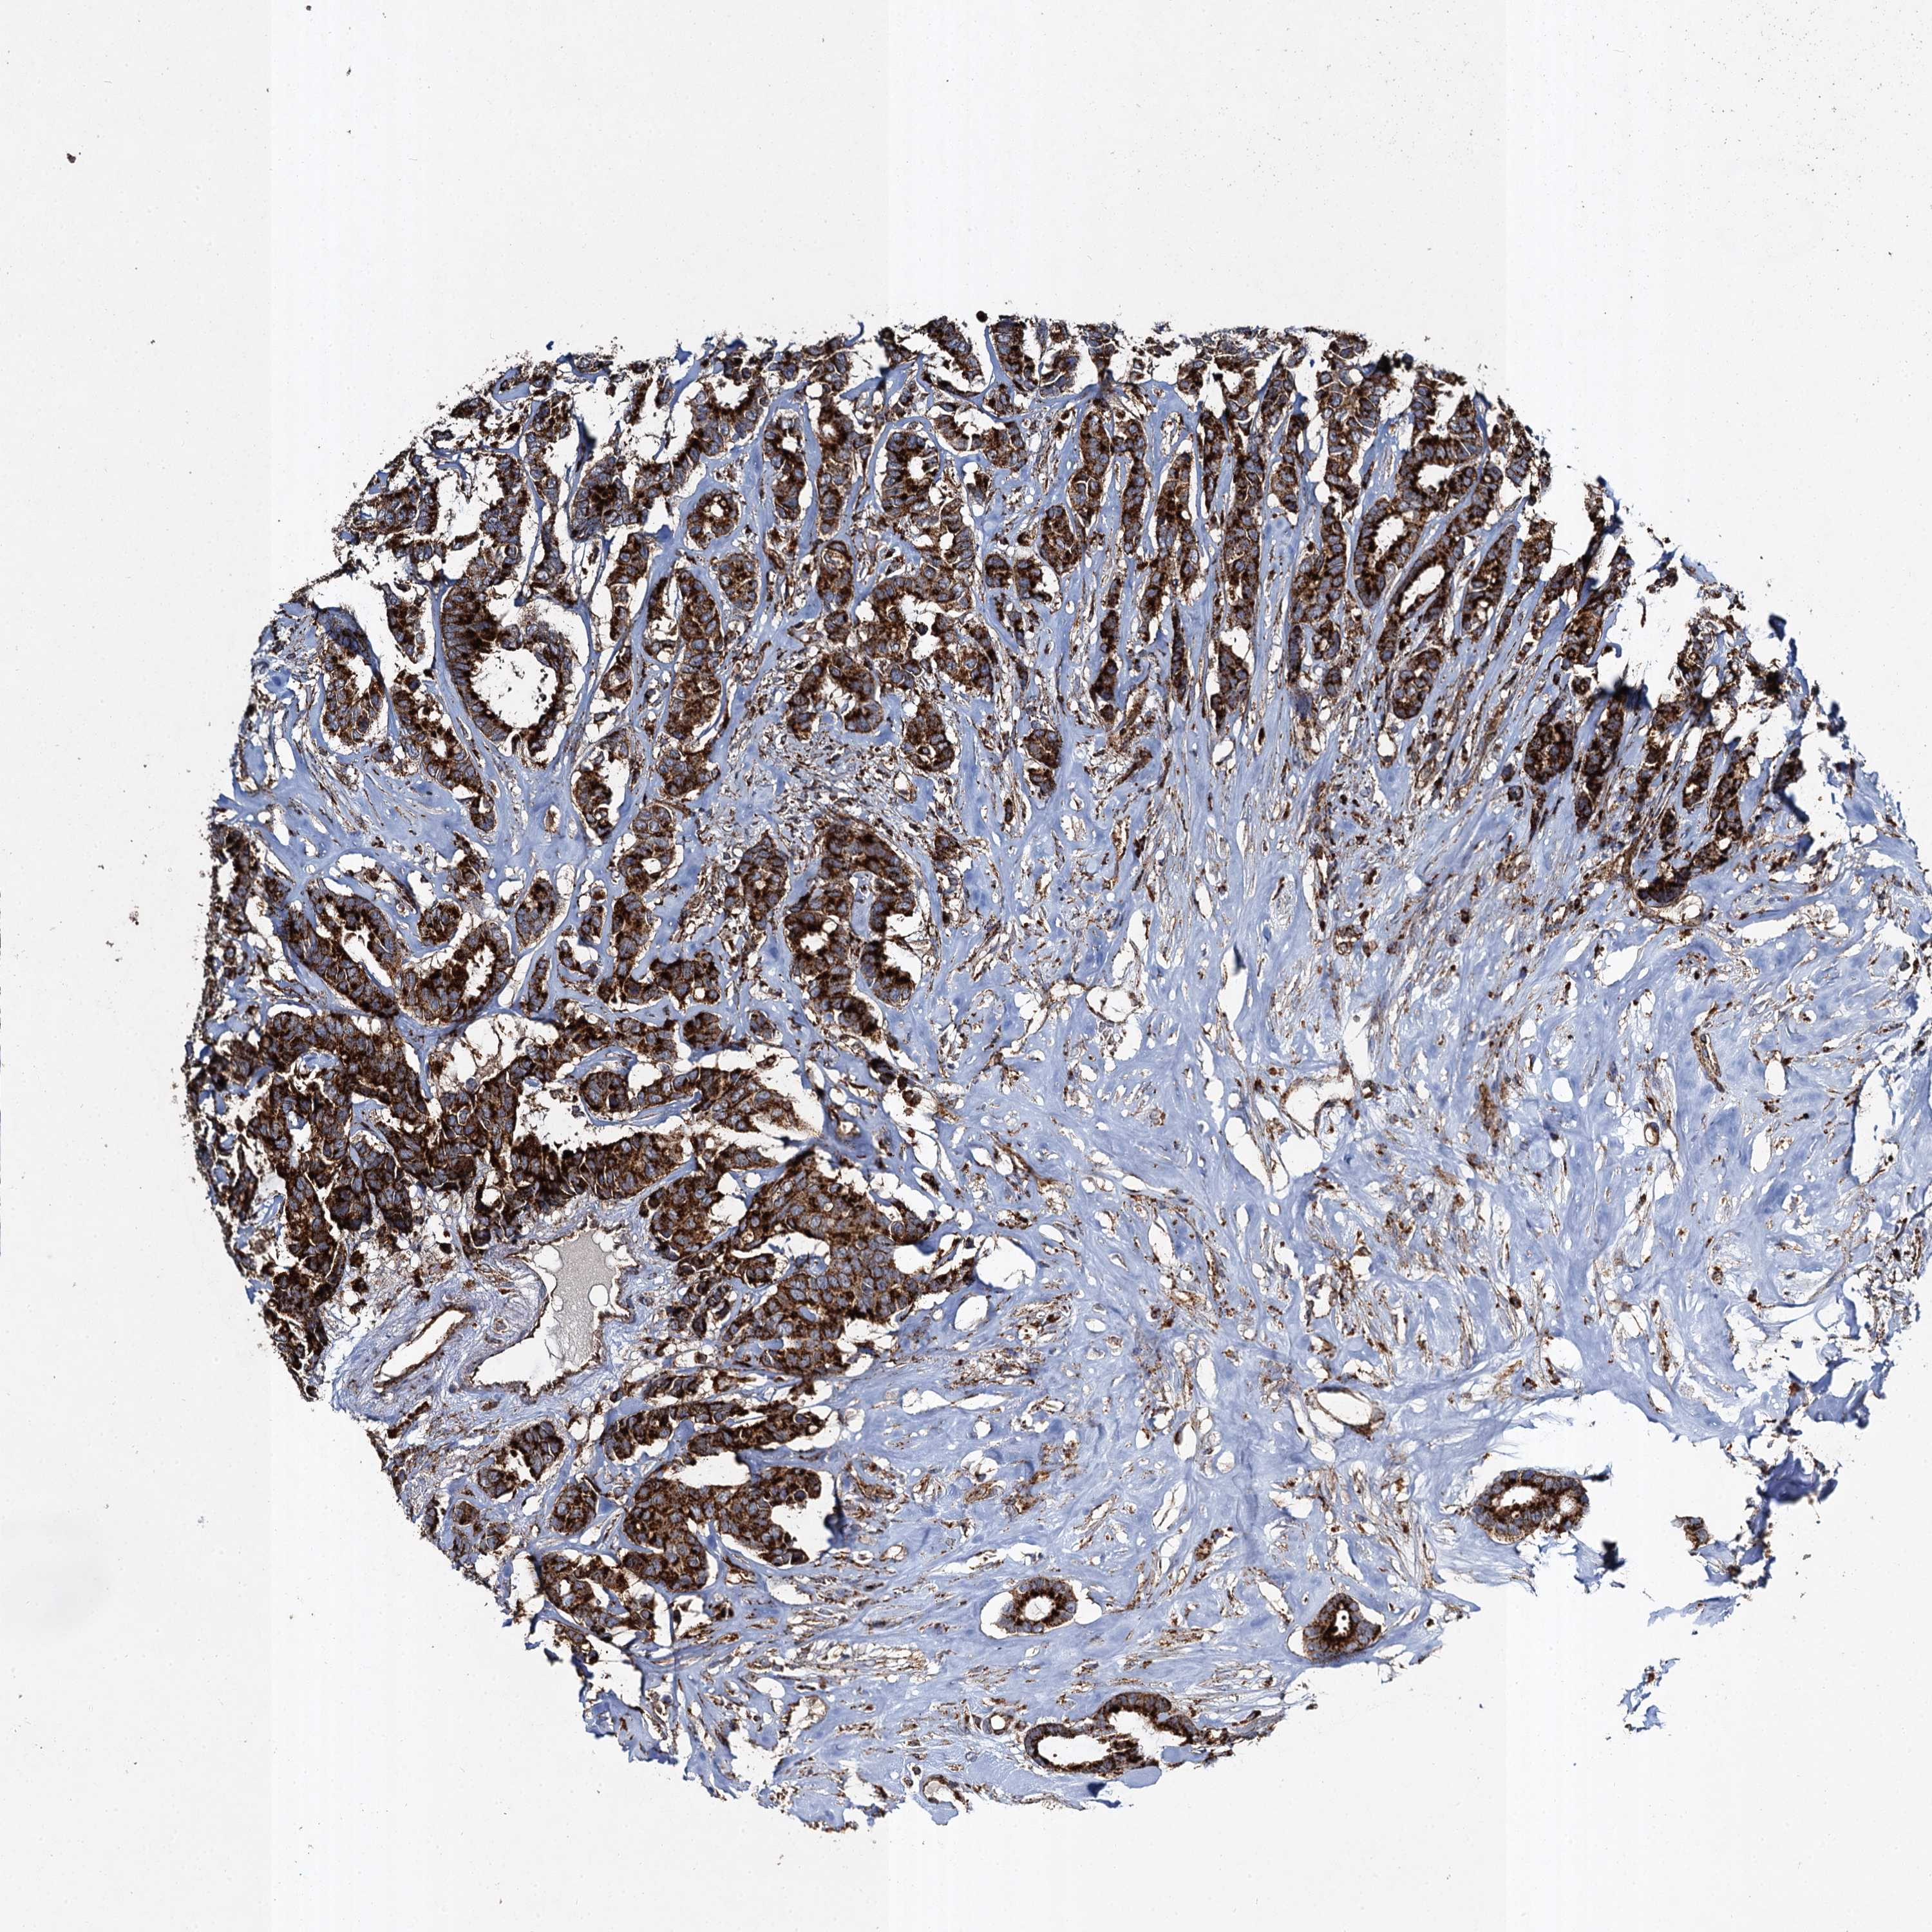

BRCA TCGA BRCA VALIDATION PROTEIN EXPRESSION

ANTIBODIES

AND

VALIDATION